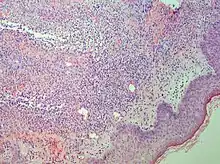

There is an elevated white blood cell count. There is infiltrates by neutrophil granulocytes on histologic examination.

Studies show a moderate neutrophilia (less than 50%), elevated ESR (greater than 30 mm/h) (90%), and a slight increase in alkaline phosphatase (83%). Skin biopsy shows a papillary and mid-dermal mixed infiltrate of polymorphonuclear leukocytes with nuclear fragmentation and histiocytic cells. The infiltrate is predominantly perivascular with endothelial-cell swelling in some vessels, but vasculitic changes (blood clots; deposition of fibrin, complement, or immunoglobulins within the vessel walls; red blood cell extravasation;inflammatory infiltration of vascular walls) are absent in early lesions.Perivasculitis occurs secondarily, because of cytokines released by the lesional neutrophils. True transmural vasculitis is not an expected finding histopathologically in SS.

Sweet described a disease with four features: fever; leukocytosis; acute, tender, red plaques; and a papillary dermal infiltrate of neutrophils. This led to the name acute febrile neutrophilic dermatosis. Larger series of patients showed that fever and neutrophilia are not consistently present. The diagnosis is based on the two constant features, a typical eruption and the characteristic histologic features; thus the eponym "Sweet's syndrome" is used.